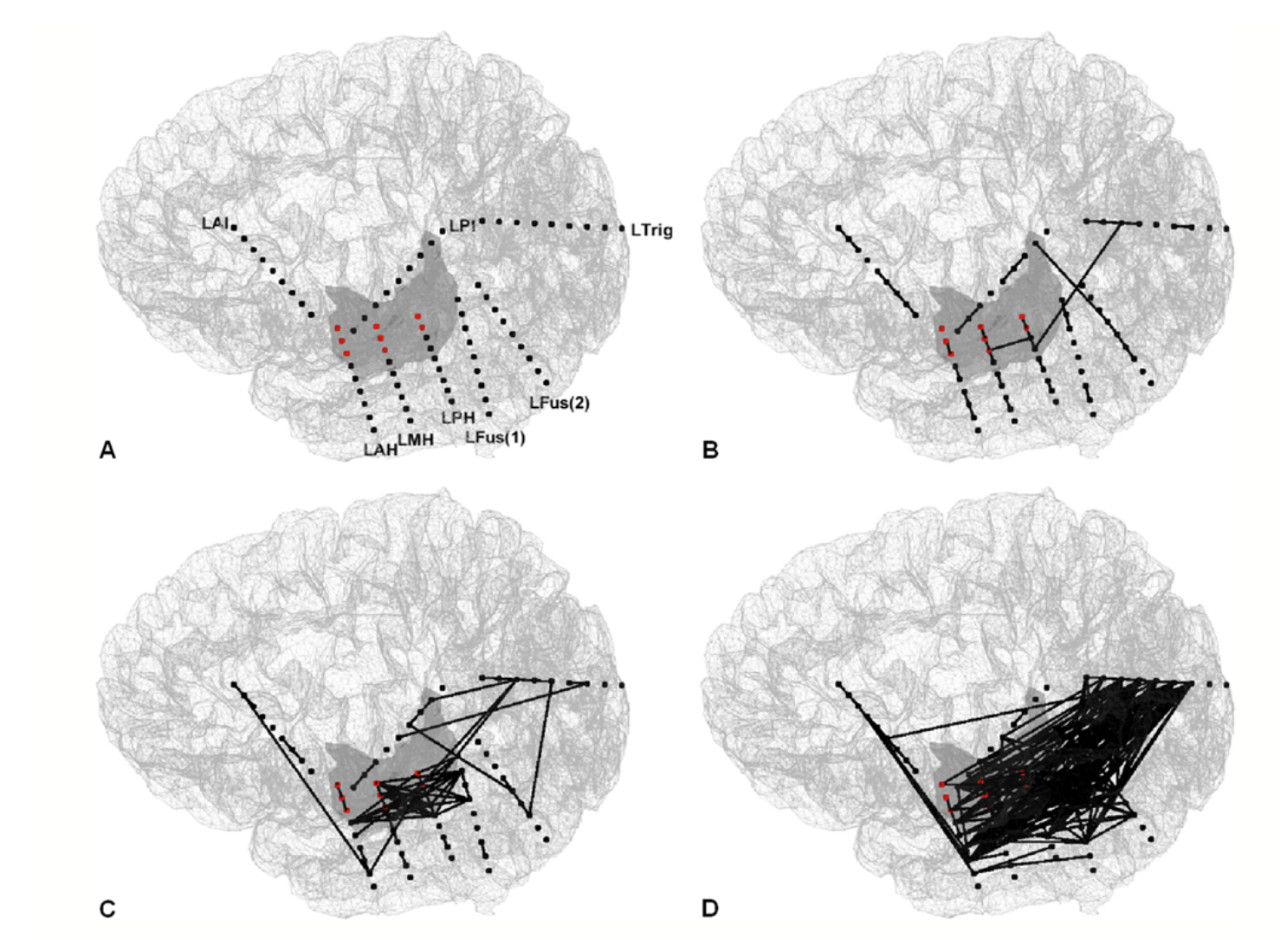

13.从SEEG高频震荡看颞叶癫痫的发作网络

Ictal networks of temporal lobe epilepsy: views from high-frequency oscillations in stereoelectroencephalography

Author: Syu-Jyun Peng, Chien-Chen Chou, Hsiang-Yu Yu, Chien Chen, Der-Jen Yen, Shang-Yeong Kwan, Sanford P. C. Hsu, Chun-Fu Lin, Hsin-Hung Chen and Cheng-Chia Lee

DOI: https://doi.org/10.3171/2018.6.JNS172844

作者研究了癫痫发作期间的高频振荡(HFO)网络,以确定HFO如何从局灶性大脑皮层扩散并在大脑的各个区域同步。作者利用自药物难治性颞叶癫痫(TLE)患者的立体脑电图(SEEG)信号,计算出所有接触对之间的接触间交叉系数,构建5例患者发生的20例癫痫发作的HFO网络。然后,他们将癫痫发作持续时间数据标准化为10个相等长度的间隔(标记为I1–I10),从而在计算出癫痫发作持续时间数据后,计算了HFO网络拓扑指标(即网络密度和组件大小)。研究发现,从皮层和皮层下HFO网络的动态拓扑结构的角度,作者观察到在I5–I10间隔期间网络密度显着增加。在I3–I8间隔期间,总能量也显着增加。子网分析的结果表明,癫痫发作后组件的数量连续减少,在I3–I10间隔期间,这些结果具有统计学意义。此外,在癫痫发作期间,大多数结点都连接到一个主要成分,并且最大部分内的结点百分比显着增加,直到癫痫发作终止。一致的拓扑变化表明TLE受常见的癫痫发作模式影响,这有助于阐明表征TLE的致癫痫网络,同时提示,包括皮层切除,皮层刺激和对网络拓扑结构敏感的神经调控在内的方式可以提高癫痫的控制率。

图:该图显示了重建的皮质表面中的各个节点(A)。红色结节位于左海马区。癫痫发作之前(-1),癫痫发作开始(间隔I1)(C)和癫痫发作中期(间隔I6)(D)的单次发作(B)的代表性网络。LAH=左前海马;LAI=左前岛;LFus(1)=左梭状回(1); LFus(2)=左梭状回(2); LMH=左中海马体;LPH=左后海马;LPI=左后岛 LTrig=左三角区。

【王军】